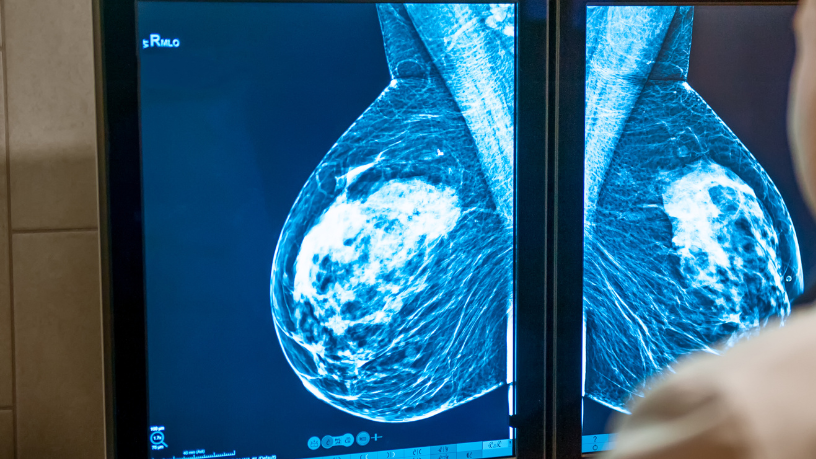

Segundo Hayashi, o diagnóstico da ginecomastia é clínico e pode ser complementado com exames de imagem e laboratoriais. Durante a consulta, o cirurgião avalia o histórico médico, hábitos de vida e uso de medicamentos, além de examinar o grau de desenvolvimento das mamas. Em alguns casos, são solicitados exames hormonais, ultrassonografia ou mamografia para descartar outras causas de aumento mamário, como acúmulo de gordura ou tumores.